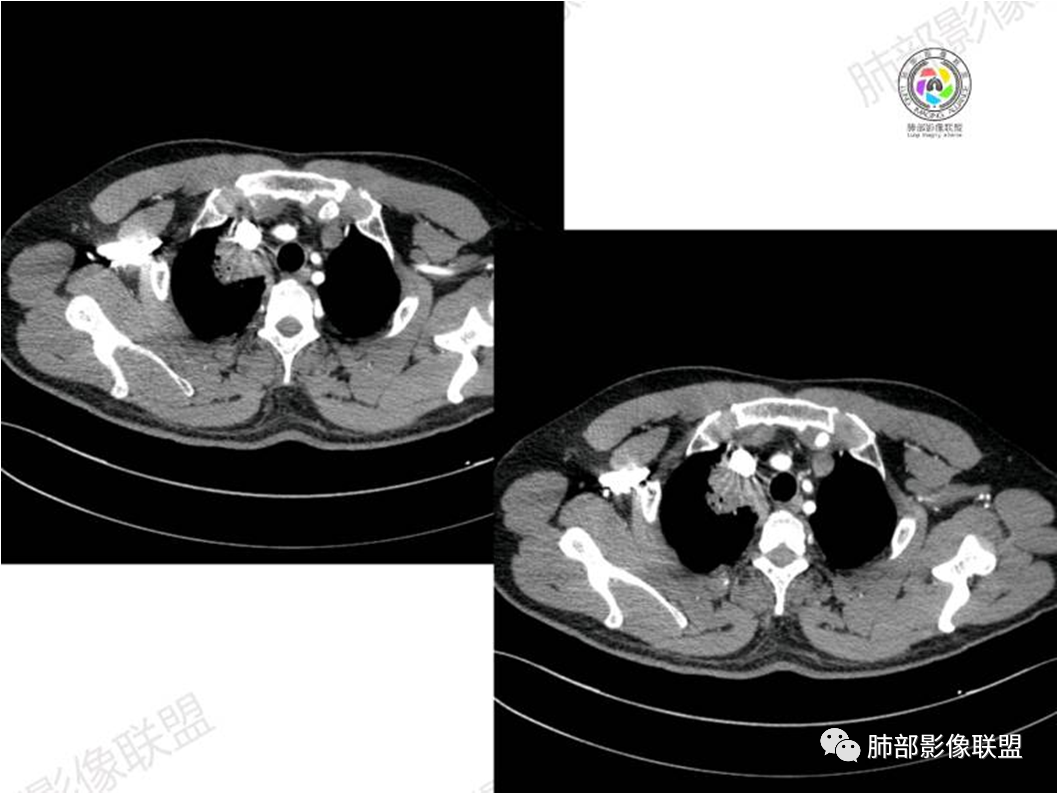

胸部CT:

中年男性,偶有咳嗽,右肺上叶近纵膈旁占位,内可见僵硬的支气管和小空泡征,病灶边缘可见分叶,毛刺,增强病灶中度以上不均匀强化,可见血管造影征,考虑恶性病变,腺癌可能性大。

右肺上叶纵隔胸膜侧一实性肿块,与纵隔胸膜宽基底相连,局部脂肪间隙消失,形态欠规则,内部可见多个小空泡,平扫密度尚均匀,增强后可见点条状强化,内部穿行血管,周围肺组织干净,纵隔淋巴结略肿大,男性44岁,只有咳嗽,考虑恶性肿瘤,腺癌,鳞癌。鉴别结核,OP,炎性假瘤。

右肺上叶近纵膈旁肿块,密度均匀,边缘分叶,毛刺,气管受压变窄,不均匀强化,可见血管造影征,考虑淋巴瘤,鉴别炎性假瘤。

中年男性,右肺上叶纵隔旁软组织肿块,边缘膨隆、毛糙,可见多发分叶,支气管穿行,部分截断,增强后密度欠均匀,纵隔内见多发小淋巴结,首先考虑恶性,腺癌,鉴别淋巴瘤

中年男性,右肺上叶纵隔旁肿瘤,稍膨隆,有毛刺,支气管穿行,远端闭塞,强化均匀,血管走行尚可,考虑淋巴瘤可能性大(支气管远端闭塞,不太符合),鉴别腺癌(气管穿行后闭塞,不太符合),op(病灶稍膨隆)

患者中年男性,咳嗽就诊,无其他不适。胸部CT:右肺上叶尖段上纵膈旁肿块,边界清楚,边缘光滑,内见支气管受压变窄,伴阻塞性改变,增强均匀强化,见血管造影征。综合考虑恶性病变,小细胞肺癌或淋巴瘤。气管镜活检应能明确。

中年男性,右肺上叶纵隔旁实性病灶,边缘有彭隆,有平直,有分叶,有尖角,病灶边缘中心可见支气管征,周围少许磨玻璃,边缘模糊,增强后动脉期病灶可见强化血管影,渐进性强化,临近血管界限清晰。考虑炎性病灶,普通炎性肉芽肿?结核?炎性肌纤维母细胞瘤?鉴别腺癌,淋巴瘤